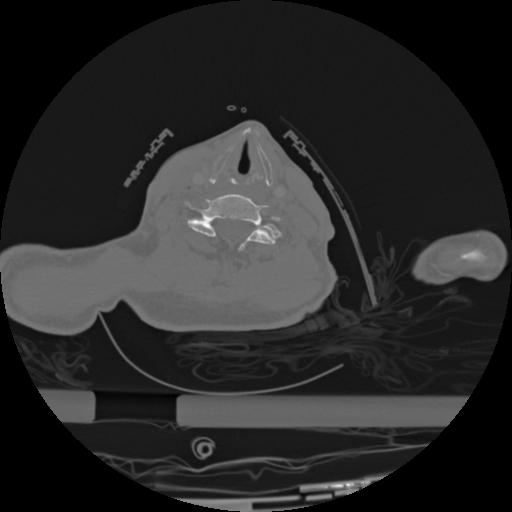

22 ANGIO,CE,Vol,0.5,ANGIO,,